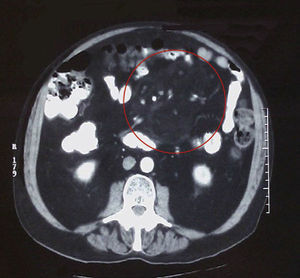

We report the case of a 65-year-old man with ankylosing spondylitis of 17 years of evolution and repeat bilateral uveitis. His spondylitis had a progressive course, which was not being controlled with anti-inflammatory drugs, so we decided to start treatment with etanercept, which was not effective. In the last eight months he presented gradual diarrhea and abdominal pain, so his case was studied by the Department of Gastroenterology, who performed a colonoscopy discarding inflammatory bowel disease. One day before admission to the General Surgery department he presented acute abdominal pain and bilious vomiting. On examination, the abdomen was distended without signs of peritoneal irritation. He had leukocytosis with elevated acute phase reactants and X-rays showed dilation of the small bowel. We proceeded to perform abdominal CT (Fig. 1) observing the “fat ring sign” characteristic of mesenteric panniculitis, which consists of the observation of surrounding heterogeneous mesenteric masses4 displacing the bowel. Faced with an episode of intestinal obstruction, fluid therapy was instituted with bowel rest, with resolution of the problem. He was subsequently followed as an outpatient; we repeated the Mantoux and Quantiferon® tests, which were negative. A year later, he remains gastrointestinally asymptomatic.